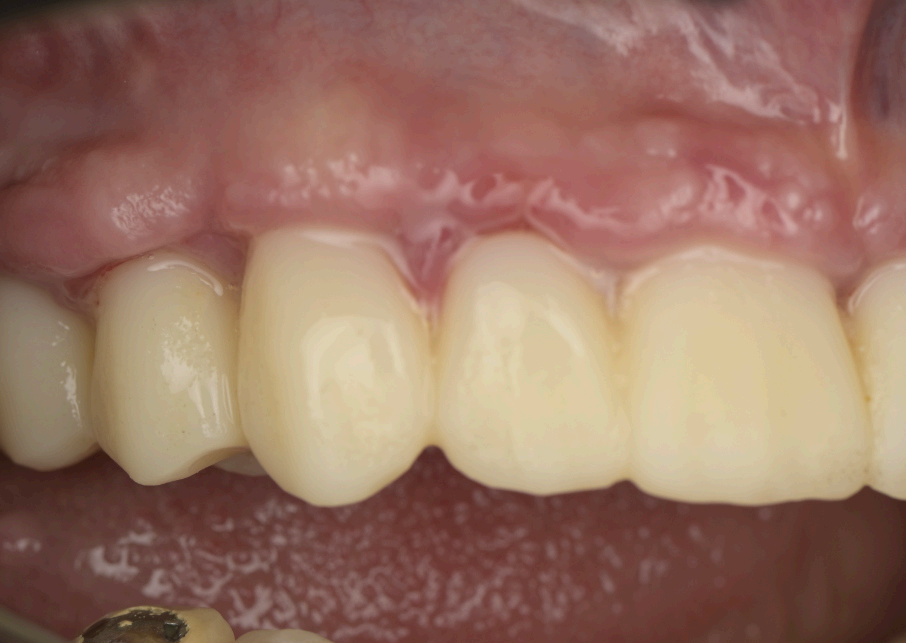

Group 4: Immediate Provisionalization and Healing Fig. 4.1: Clinical photo of the 3D-printed provisional prosthesis inserted on the day of surgery. Fig. 4.2: Gingival healing at two months with emerging scalloped contours. Fig. 4.3: Application of BlueM gel for tissue and prosthesis disinfection. Fig. 4.4, 4.5: Post-cleaning views of healthy gingival tissues.

The immediate provisional prosthesis was designed in Exocad, incorporating screw channel holes for fxation to the MUAs (Fig. 3.8). The design prioritized a scalloped emergence profle to support the soft tissues and guide their adaptation during healing. The prosthesis was 3D-printed in resin and delivered to the patient on the same day as the surgery, achieving a secure ft and immediate functionality (Fig. 4.1). The precision afforded by the Shining3D Elite’s photogrammetry ensured that the provisional seated passively, minimizing adjustments and enhancing patient comfort.

At three months post-surgery, the soft tissues exhibited a mature, festooned contour that enhanced the aesthetic integration of the prosthesis (Fig. 6.1, 6.2). The refned provisional had successfully guided this outcome, with the gingival margins aligning seamlessly with the prosthetic teeth (Fig. 6.3–6.6). The fnal zirconia-iBar prosthesis demonstrated excellent stability, with no signs of mechanical complications or peri-implant infammation (Fig. 7.1). Aesthetically, the restoration fulflled the patient’s expectations, achieving a natural smile with balanced proportions and a lifelike gingival appearance. Functionally, the patient reported full satisfaction with mastication and speech, indicating a successful rehabilitation.